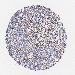

STOMACH CANCER - Protein expressioni

A mouse-over function shows sample information and annotation data. Click on an image to view it in a full screen mode. Samples can be filtered based on level of antibody staining by selecting one or several of the following categories: high, medium, low and not detected. The assay and annotation is described here.

Note that samples used for immunohistochemistry by the Human Protein Atlas do not correspond to samples in the TCGA dataset.

Antibody stainingi

Antibody staining in the annotated cell types in the current human tissue is reported as not detected, low, medium, or high, based on conventional immunohistochemistry profiling in selected tissues. This score is based on the combination of the staining intensity and fraction of stained cells.

Each image is clickable and will lead to virtual microscopy that enables deeper exploration of all samples and also displays staining intensity scores, fraction scores and subcellular localization as well as patient and tissue information for each sample.

Antibody CAB002003

Staining

High

Medium

Low

Not detected

Intensity

Strong

Moderate

Weak

Negative

Quantity

>75%

75%-25%

<25%

None

Location

Nuclear

Cytoplasmic/membranous

Cytoplasmic/membranous,nuclear

Adenocarcinoma, NOS